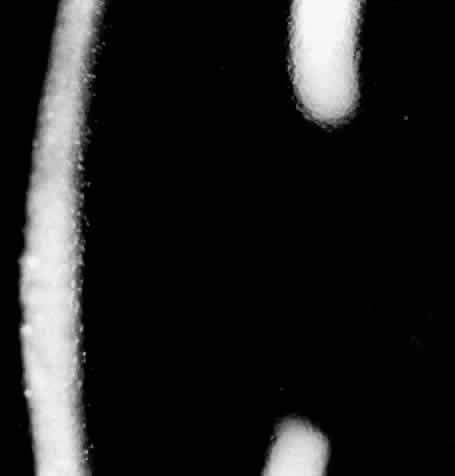

Clinically, the cornea has a ground-glass appearance owing to significant stromal edema, but the epithelium only shows a granular appearance without staining (Fig. 13). No bullous changes are seen. Band keratopathy may be an associated finding. Erosions are unusual. Visual acuity ranges from 20/50 to light perception. No consistent systemic findings have been demonstrated. However, one family displayed an autosomal dominant pattern in which high-tone sensory deafness was present. The parents were first cousins.205 Family history and clinical findings are important in differentiating this dystrophy from other diseases.206,207 It is especially important to rule out congenital glaucoma which requires different management. Consanguinity may increase risk of systemic problems.

Fig. 13. Congenital hereditary endothelial dystrophy: haziness secondary to edematous thickened stroma.